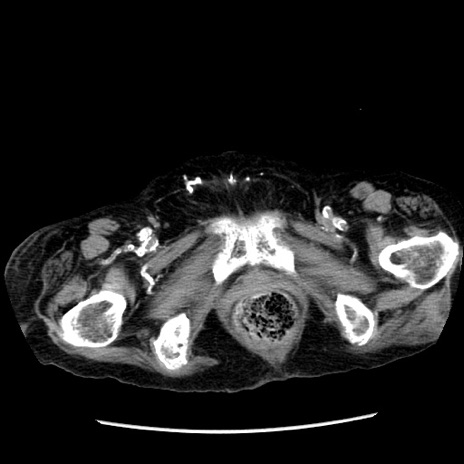

症例14(横断像)

【症例】 90歳代女性

【主訴】 腹痛・嘔吐

【現病歴】今朝から左側腹部痛を認めた。 経過観察していたが、嘔吐を認めたため来院。

【既往歴】 子宮癌術後

【身体所見】 意識清明、BP 127/54mmHg、P 98bpm Sp02 95%(RA)、BT 35.8°C、腹部平坦・軟腸ぜん動音聴取良好、右下腹部圧痛(+) 反跳痛なし

【データ】WBC 9800、CRP 0.46